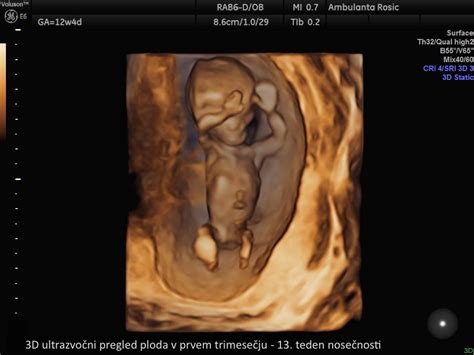

V tehničnem smislu sta 3D in 4D ultrazvok sestavljena iz niza zaporednih dvodimenzionalnih slik. Tretja dimenzija omogoča boljše merjenje volumnov in prikazuje tridimenzionalno sliko telesnih značilnosti, medtem ko četrta dimenzija doda časovno komponento, kar omogoča opazovanje gibanja ploda v realnem času. Dandanes se 3D in 4D ultrazvok najpogosteje uporabljata za prikazovanje določenih delov plodovih teles staršem, da si lahko bolje predstavljajo svojega otroka. Kljub temu pa je količina dodatnih diagnostičnih informacij s tema dvema tehnologijama odvisna od usposobljenosti ginekologa. Glavna prednost je v tem, da računalniški prerez skozi 3D posnetek omogoča pridobivanje ravnin, ki jih z 2D tehniko v živo ne bi mogli dobiti.

Osnovna razlika med različnimi vrstami ultrazvoka je v tehniki prikaza. 2D ultrazvok je dvodimenzionalen in črno-bel. 3D ultrazvok predstavlja tridimenzionalno računalniško rekonstrukcijo slike, medtem ko 4D ultrazvok dodaja še časovno komponento, kar omogoča opazovanje gibanja ploda v realnem času. Nosečnica lahko domov dobi fotografijo ali CD le ob predhodnem dogovoru, te storitve pa so praviloma plačljive.